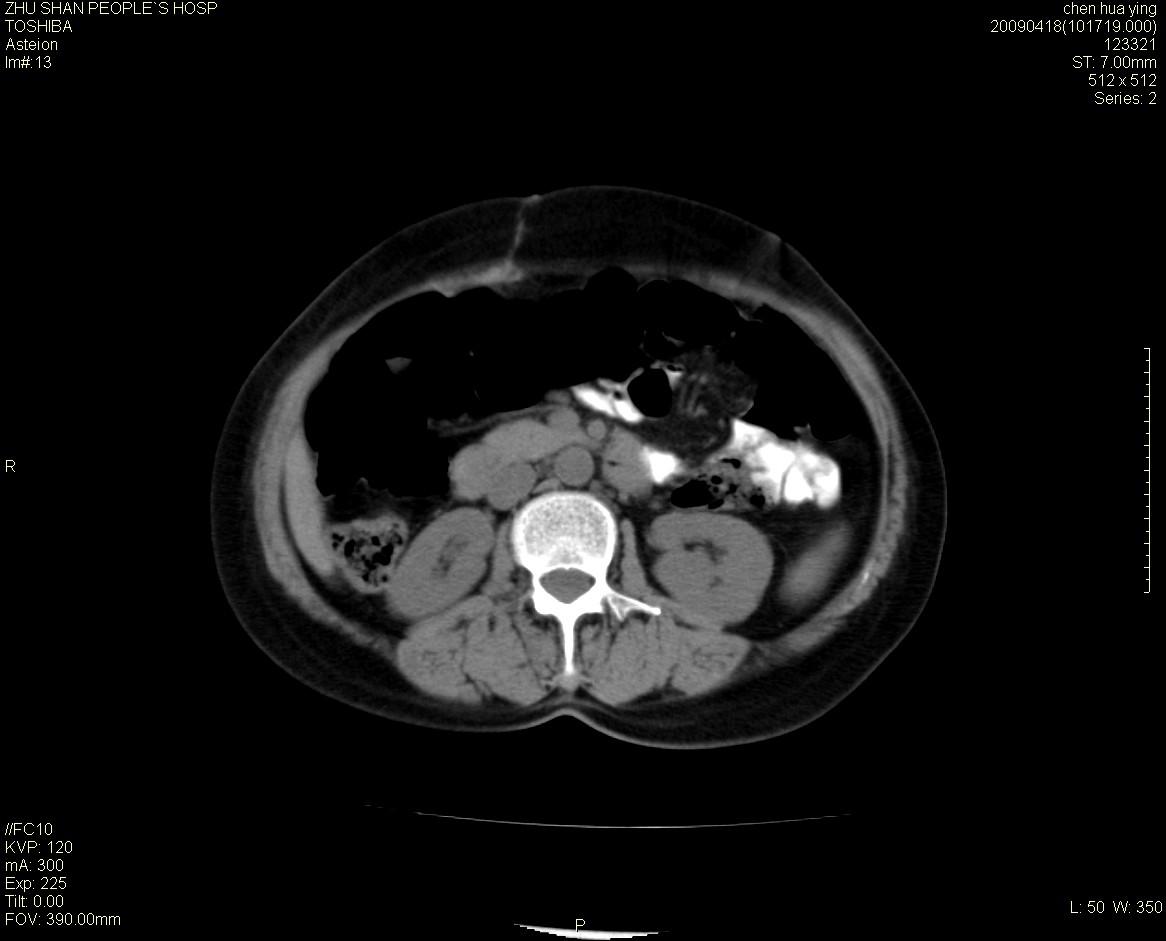

女性病人 65岁 腹部包块半年余结肠造影未见异常.

病灶略呈圆形有分叶状,上部层面呈实性,右侧见圆形低密度区,灶内见团块状钙化,病灶下方与肠管分境不清,考虑间质瘤可能性大,建议肠道准备后增强